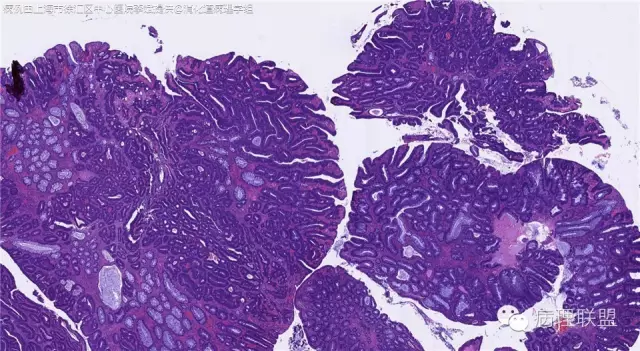

男,72岁,距肛门口30cm息肉。大体:灰白结节1.5*1*0.8cm拟发管状腺瘤并部分区高级别,请各位老师指导!(病例由上海市徐汇区中心医院 李斌 提供,致谢!)

这一例有两种不同看法,按WHO标准,为高级别,按实际工作,要发粘膜内癌。WHO第三版与第四版均提出,侵犯至粘膜下层才能诊断为癌,声称结直肠粘膜内没有淋巴管,发生转移的概率较小,但是粘膜内有血管,肿瘤侵出粘膜腺体基膜以外,就能侵犯血管,照样可以发生血道转移。文献报告与我们的工作实践,发现腺瘤、高级别(没有侵出基膜)的患者,同样有发生血道转移。因此,我们废弃了这一条WHO标准(不是所有的WHO标准都是一定要执行的)。只要异型增生腺体呈毛刺状、迷芽状侵出粘膜腺体基膜,位于粘膜肌层以内,就发粘膜内癌。

@李斌 结肠腺瘤这例我认为已经有黏膜下浸润了,因为有些腺体间的间质已经不是固有膜间质而是促结缔组织增生反应的间质了。但即使有浸润癌,如果息肉完整摘除、癌成分分化好、没有脉管瘤栓、浸润癌距切缘大于1mm(日本标准还要看浸润癌超出黏膜肌深度和肿瘤出芽情况),也不需要进一步治疗。所以,对于这类可能存在争议的病变,特别是息肉已经完整切除的病例,诊断的关注点就应该放在寻找需不需要进一步治疗的证据上了。@邓永键 2010版WHO在腺瘤部分的陈述中已经写出对于有局灶浸润性生长的病例也可以称黏膜内癌,他们在悄悄的让步。